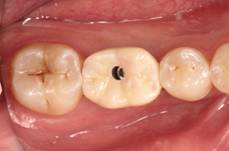

种植治疗是一种以植入骨组织内的下部结构(种植体)为基础来支持/固位上部修复体的缺失牙修复方式,是治疗牙齿缺失的一种较新的、成熟的临床技术。医生需要根据理想的缺失牙修复方案所要求的植体分布和三维方向、结合患者口腔局部和全身条件,设计制定合理的种植外科方案后,经手术方法将种植体植入组织内(通常是上下颌)、并获得骨组织牢固的固位支持,最后通过特殊的装置和方式连接支持上部的修复体。目前常用的种植体材料主要是钛、上部暴露于口腔内的修复体材料趋同于天然牙修复材料。

修复导向种植治疗方法的主要优点是主要依靠种植体的支持,恢复缺牙区的软硬组织形态、实现预期的功能与美学目标,这种方式更加符合口腔生物力学的要求,从而有利于获得更为长期的修复成功率。

(图片由修复科韩彦峰医生提供)